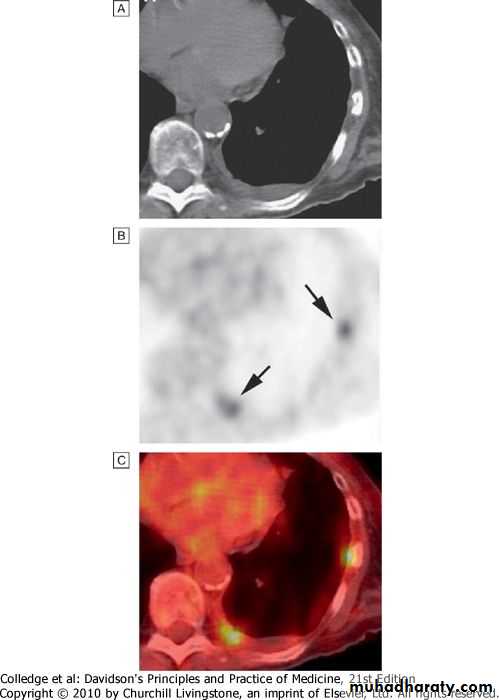

Positron emission tomography (PET)

PET scanners exploit the avid ability of malignant tissue to absorb and metabolise glucose..